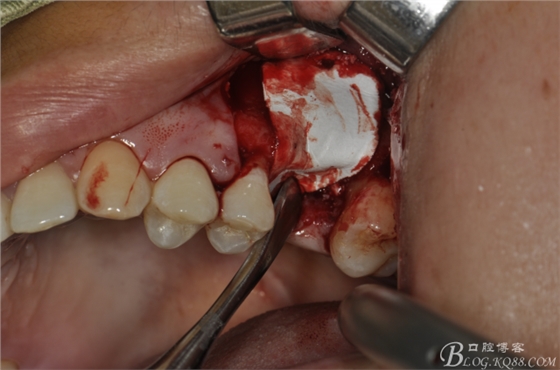

術(shù)中照片。